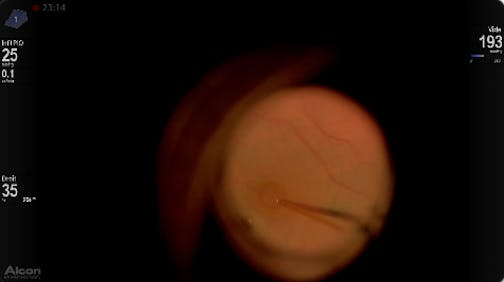

High Myopia and Macular Hole

Patricia Udaondo, MD